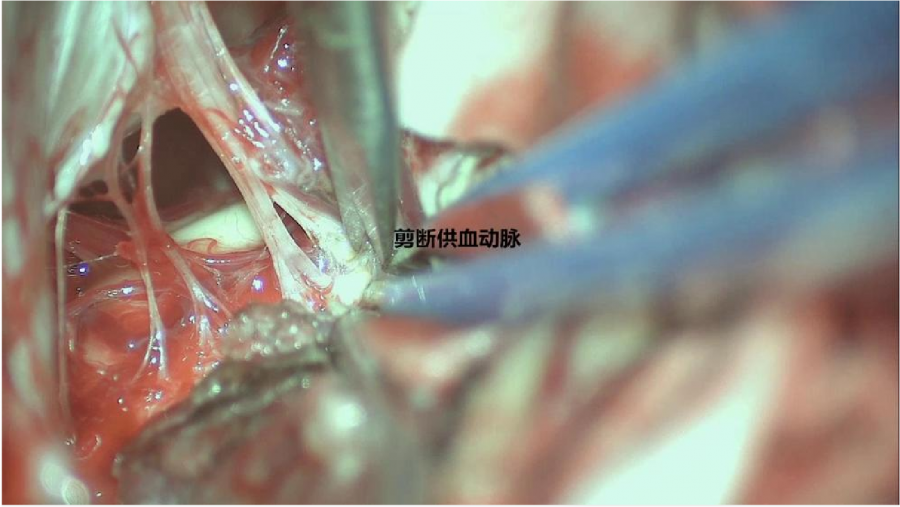

⾏左侧远外侧⼊路脑⼲⾎管畸形切除术,术中所⻅:

3、脑⼲动静脉畸形⼿术切除是注意辨别供⾎动脉与引流静脉,其往往不似其他部位的动静 脉畸形,有叫粗⼤的引流静脉。术中如果不能辨清各⾎管来源与去处,往往会造成不可估量的损失。